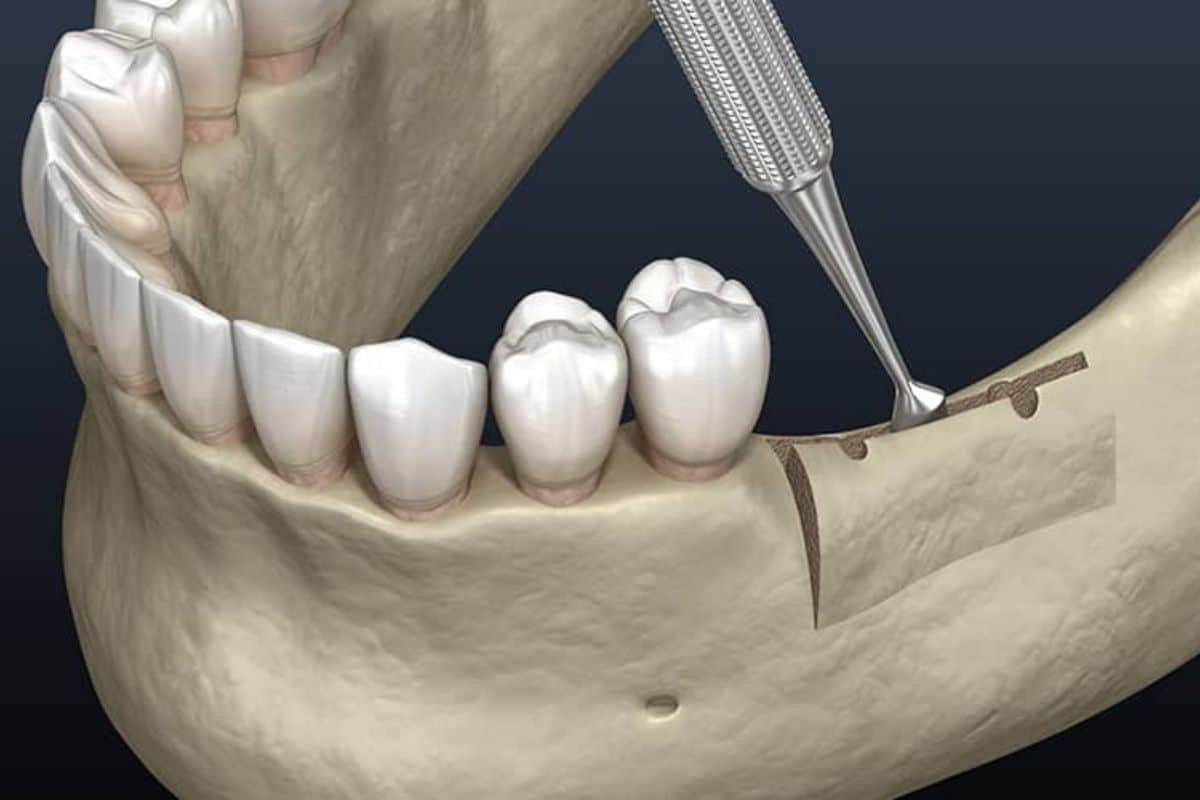

- Surgical Procedure

- During surgery, the dentist makes an incision in the gum to expose the jawbone. The graft material is then placed in the area where bone is deficient, and it is carefully shaped to restore the ridge to its natural dimensions.

- In some cases, membranes or collagen plugs are used to protect the graft and encourage healing.

- After placing the graft, the gum is sutured, and the healing process begins.